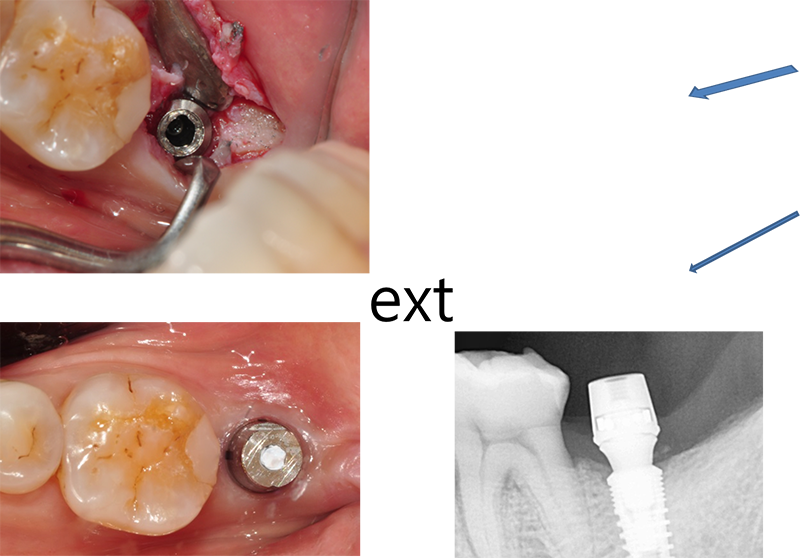

¾î¹þÀ» Ç®´Ù°¡ Ç÷¿Æû¿¡ ÀÖ´Â

Çí»ç°¡ ¸Á°¡Á³´Ù. Ç® ¼ö°¡ ¾ø¾ú´Ù. 4.4 mm ³»°æÀ» °¡Áø solid ab ü°á µå¶óÀ̺긦 ÀÌ¿ëÇϱâ·Î Çß´Ù.

¸ÕÀú Ezc ¾î¹þÀÇ Á÷°æÀ» ´ÙÀ̾Ƹóµå ¹ö·Î »ì¦ ´ÙµëÀº ´ÙÀ½, ½½·ÔÀ» ¸¸µé°í, À̰÷¿¡ solid ab µå¶óÀ̹ö°¡ »ðÀԵǵµ·Ï ÇÑ´Ù. µ¹¸®¸é ½±°Ô Á¦°ÅµÈ´Ù.

ÀÕ¸öÀÌ ¿ôÀÚ¶ú´Ù.

Emergence profile¸¦ °Á¶ÇÏÁö ¾Ê´õ¶óµµ

ÀÕ¸öÀÌ ¿ôÀÚ¶ó¼ ÀÚ¿¬½º·´°Ô µÉ ¶§µµ ¸¹´Ù. ±×·¡¼ Ezc abutment¸¦ ¼±ÅÃÇÒ ¶§ °¡´ÉÇÑ equi-gingiva ÀÌ»óÀ¸·Î ¸ÂÃß´Â °Ô À¯¸®ÇÏ´Ù.